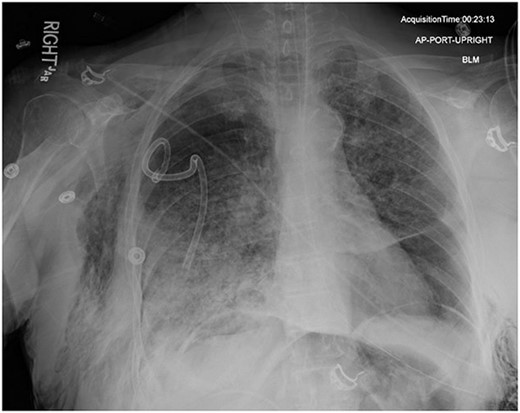

In the operating room (OR), the patient underwent intubation for TBNA using the Monarch® robotic bronchoscopy platform. Nine needle aspirations were obtained from the third-order RLL bronchi with each aliquot subjected to rapid on-site examination. While awaiting results, the patient developed retching, hemoptysis, bronchial bleeding from the superior segment of the RLL lobe and hypotension. The bleeding was managed with ice-cold saline and epinephrine. The patient required aggressive resuscitation with crystalloid, blood products and vasopressor therapy. She was transferred to the ICU where she remained intubated for ongoing resuscitation. In the ICU, the patient developed recurrent hypotension. Chest X-ray (CXR) revealed a right-sided pneumothorax (Fig. 1) that was treated with a small-bore pigtail chest tube and resulted in immediate improvement of her tension physiology. The pneumothorax resolved on repeat chest film while the patient remained intubated and sedated (Fig. 2).